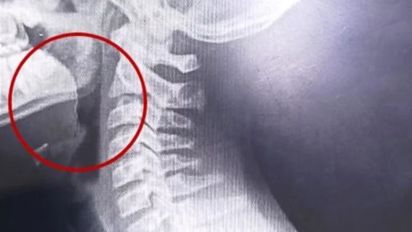

Los profesionales del Hospital Materno Infantil de Mar del Plata utilizaron equipos de alta complejidad para detectar el cuerpo extraño que obstruía las vías respiratorias del joven.

La situación cambió radicalmente cuando ingresaron al Hospital Materno Infantil. Allí, los médicos comprendieron la urgencia del caso y ordenaron la internación inmediata del menor. Tras realizar una serie de radiografías, los especialistas detectaron una sombra inusual en el tracto respiratorio superior del chico.

Para resolver el enigma, los cirujanos realizaron una laringoscopía de emergencia. Durante el procedimiento, descubrieron el origen de todo el drama: un alambre fino y filoso se había incrustado profundamente en las paredes de la garganta. Al parecer, el filamento metálico se encontraba oculto dentro de la galletita de agua que el joven ingirió minutos antes.